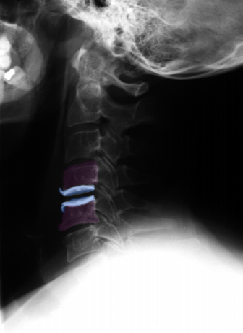

Πρόσθια αυχενική δισκεκτομή και τοποθέτηση τεχνητού αυχενικού δίσκου (μπλέ) Α6-Α7. Ακτινογραφίες με τον αυχένα σε ουδέτερη θέση (αριστερά), έκταση (κέντρο) και κάμψη (δεξιά). Αναδεικνύεται η κίνηση στο χειρουργημένο μεσοσπονδύλιο διάστημα. |